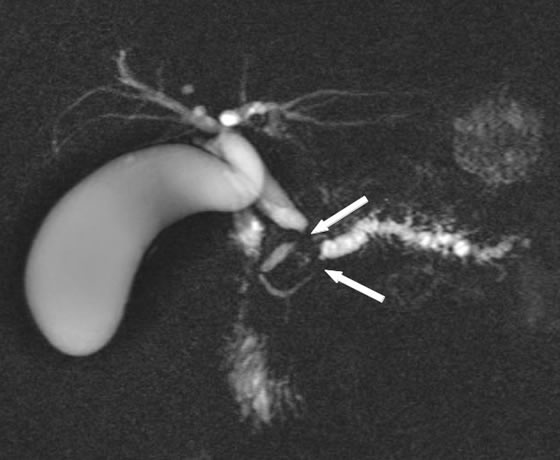

Kernspintomographie

Besonders bei einer Gelbsucht (Ikterus), die durch eine Abflussbehinderung der Gallenflüssigkeit in den Dünndarm hervorgerufen wird, spielt die Kernspintomographie der Bauchspeicheldrüse und die Darstellung der Gallenwege und Gänge der Bauchspeicheldrüse eine wichtige Rolle. Auch diese Untersuchung kann vom Hausarzt als erste Bildgebung bereits durchgeführt worden sein. In der MRT (Magnet-Resonanz-Tomographie) können die flüssigkeitsgefüllten Gänge der Leber über die Gallenwege und der Bauchspeicheldrüse sehr genau beurteilt werden.